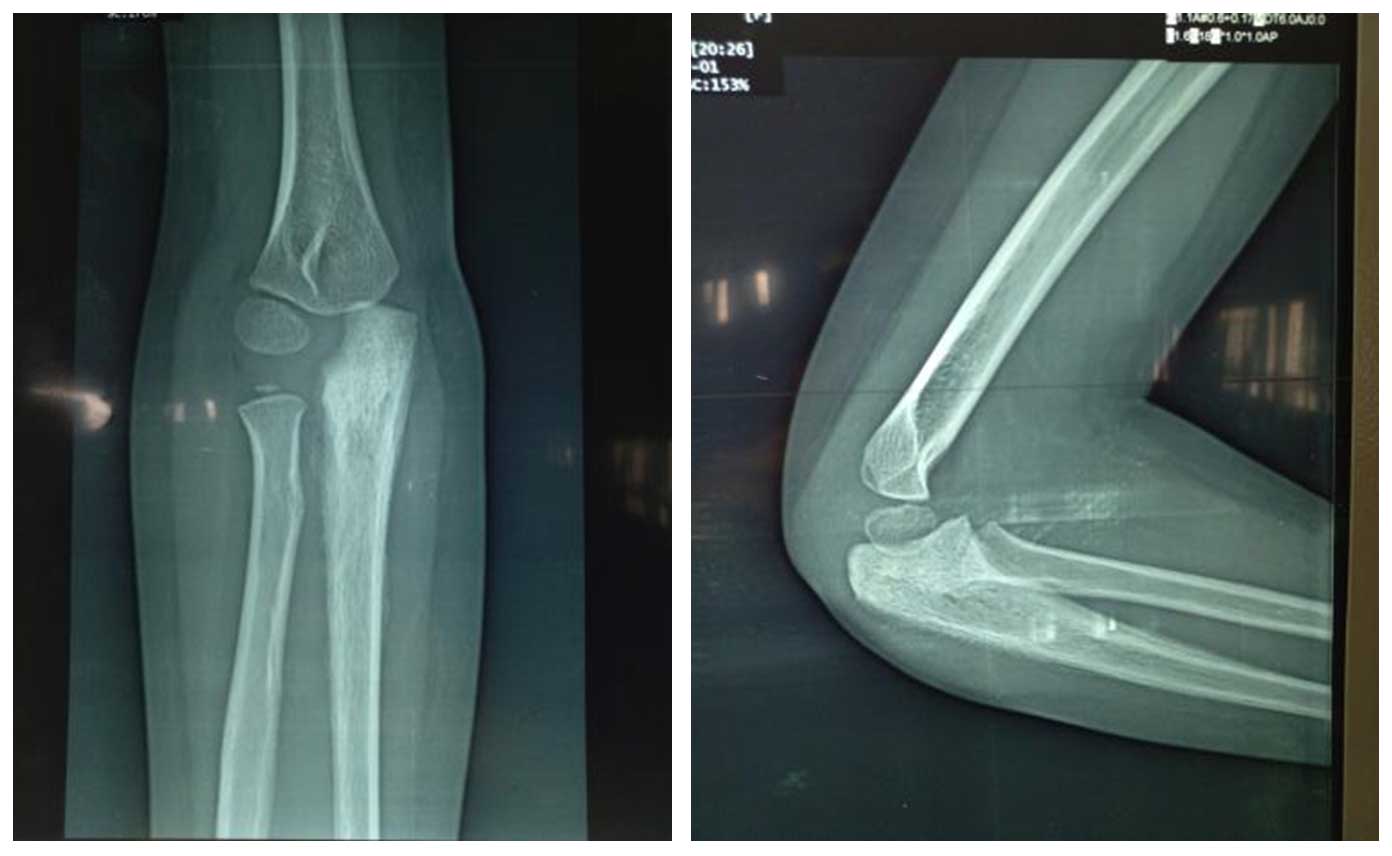

Ameliyat Öncesi: Röntgende proksimal ulnada skleroz, düzensizlik ve periost reaksiyonu görülmekte.